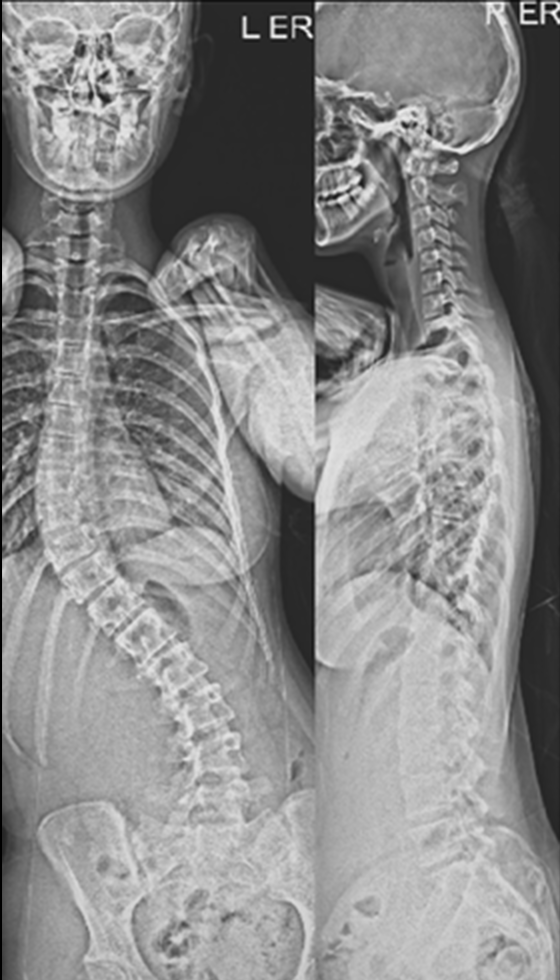

Gallery : Before - After